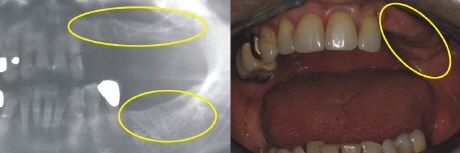

Ausgangssituation

Das Röntgenbild zeigt es (gelbe Kreise). Die gesamten Seitenzähne (Kauzähne) auf einer Seite, sowohl unten als auch oben, fehlen. Dadurch fehlt die ganze funktionell wichtige Abstützung der Kiefer zueinander.